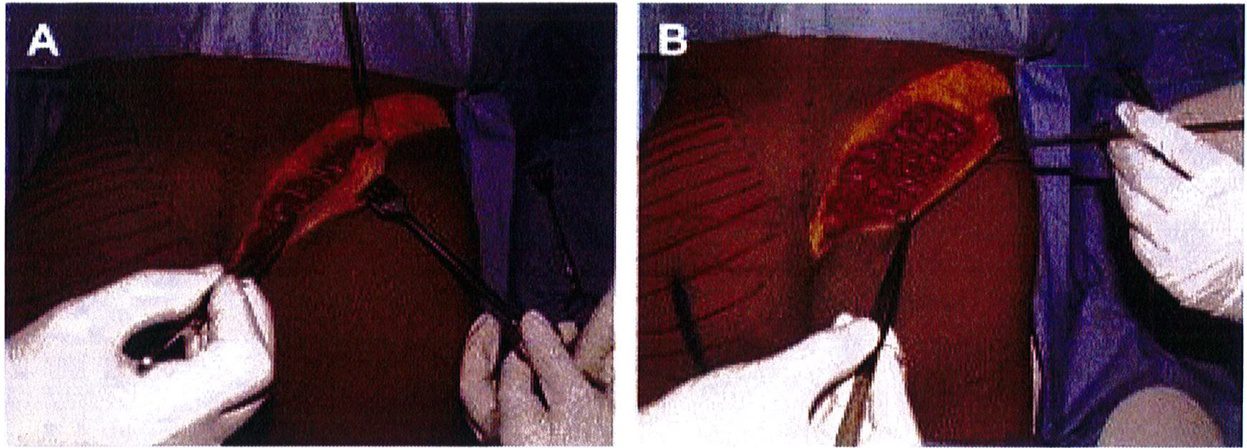

Hình. 6. Rạch da cạnh xương cùng, thực hiện bóc tách theo một góc nghiêng từ đường rạch tới giới hạn là đường bờ ngoài xương cùng. Sau đó tiếp cận tới lớp cân nông, rạch cân và đặt túi cấy dưới cân, trên bề mặt cơ mông lớn. (Trích từ de la Pena JA, Rubio OV, Cano JP, et al. Subfascial Nâng mông. Clin Plast Surg 2006;33÷411; đã xin phép trước khi đăng tải.)

Bệnh nhân ở tư thế đứng, đánh dấu vị trí khối implant theo

tiêu bản như hình 4. Tiêu bản này phải được đặt chính giữa vùng mông, cách nếp lằn mông ít nhất 5cm và đường liên gai ít nhất 2cm (Hình. 5).